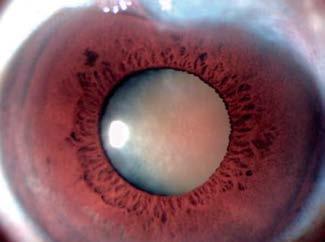

El resultado postoperatorio validó la elección de la técnica. La paciente alcanzó una mejoría visual significativa, pasando de cuenta dedos a 20/40. En el seguimiento, se observó la lente centrada, el túnel sellado y una PIO estable de 9 mmHg (Figura 7A). La ampolla filtrante permaneció funcional y sin cambios morfológicos respecto al estado preoperatorio (Figura 7B).

Figura 7A. Conjuntiva temporal en el postoperatorio

Figura 7B. Ampolla filtrante posterior a MSICS